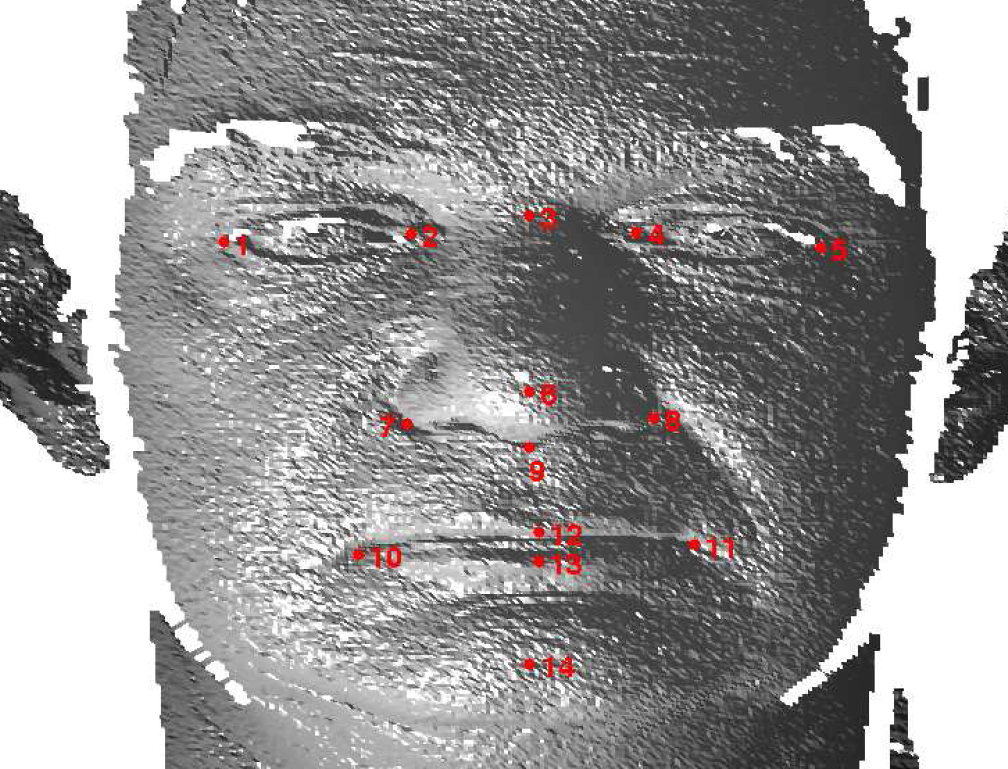

Referring to Fig. 5, our method is a supervised learning technique - landmarks are marked by hand on a set of training images. We used 279 faces (each different individuals) in the Face Recognition Grand Challenge (FRGC) dataset [26]. The landmarks used are described in table 1 111Some descriptions taken from www.facebase.org and can be seen on an example FRGC 3D face scan in Fig. 7.

| ID | Name | Description |

|---|---|---|

| 1 | Right exocanthion | Right outer eye corner |

| 2 | Right endocanthion | Right outer eye corner |

| 3 | Nasion | The midline between the orbits, vertically at the |

| level of the uppermost sulci created by the eyelids. | ||

| 4 | Left endocanthion | Left inner eye corner |

| 5 | Left exocanthion | Left outer eye corner |

| 6 | Pronasale | The most protrusive point on the nasal tip |

| in the midline. | ||

| 7 | Right alar curvature point | Junction of the right nasal alare and upper lip |

| 8 | Left alar curvature point | Junction of the left nasal alare and upper lip |

| 9 | Subnasale | The apex of the nasolabial angle in the midline, |

| where the inferior border of the nasal septum | ||

| meets the upper lip. | ||

| 10 | Right chelion | Right mouth corner |

| 11 | Left chelion | Left mouth corner |

| 12 | Labiale superius | Centre of upper lip on vermillion line |

| 13 | Labiale inferius | Centre of lower lip on vermillion line |

| 14 | Pognion | Most anterior midpoint of the chin. |

The mean configuration of these landmarks is determined by Generalised Procrustes Analysis (GPA) [5] and then put into a standard frontal pose, ensuring that the best fit plane for the symmetry plane landmarks lies in the yz-plane and the subnasale and nasion are at the same depth (z coordinate).